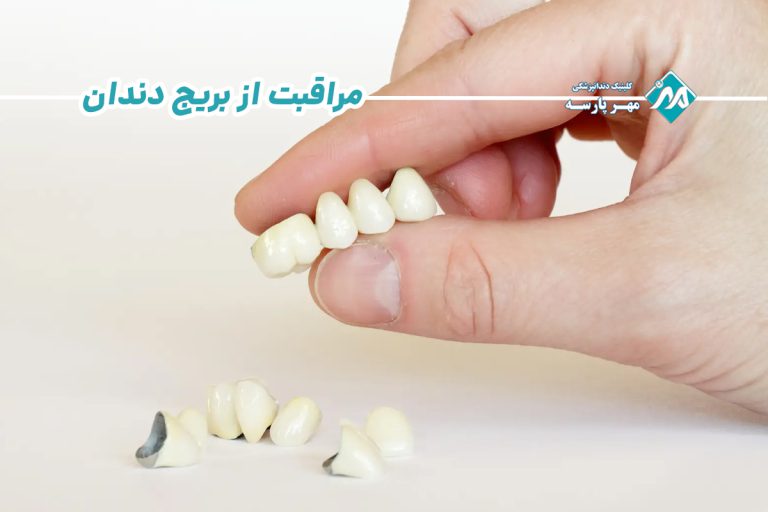

بریج دندان میتواند هم زیبایی لبخند و هم عملکرد جویدن را بازگرداند، اما دوام آن به مراقبت صحیح پس از نصب بستگی دارد. در کلینیک